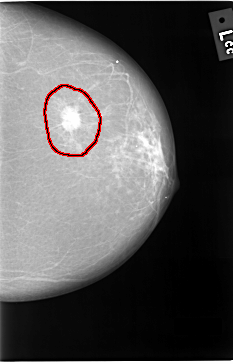

C_0037_1.LEFT_CC

LEFT_CC LINES 5816 PIXELS_PER_LINE 3720 BITS_PER_PIXEL 12 RESOLUTION 50 OVERLAY

FILE: C_0037_1.LEFT_CC.OVERLAY

TOTAL_ABNORMALITIES 1

ABNORMALITY 1

LESION_TYPE MASS SHAPE IRREGULAR MARGINS ILL_DEFINED

ASSESSMENT 5

SUBTLETY 5

PATHOLOGY MALIGNANT

TOTAL_OUTLINES 1

BOUNDARY